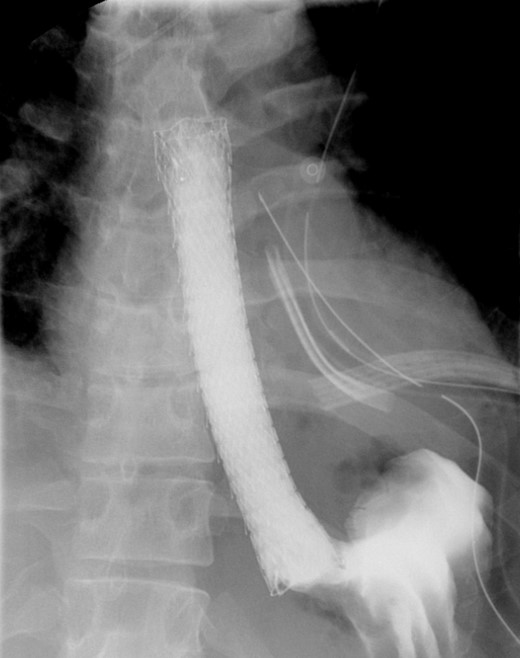

A computed tomographic scan revealed air and fluid surrounding the esophagus (Fig. 1). Esophagogram performed with water-soluble contrast media showed a distal esophageal perforation with a free leak into a large mediastinal cavity to the left of the esophagus (Fig. 2). The patient was triaged directly to the operation room. A left chest tube was placed with improvement in his oxygenation, and grossly murky fluid was drained. Esophagogastroduodenoscopy (EGD) was performed next and revealed a very small caliber esophagus with concentric ringed appearance. A tight stricture was noted in the mid-esophagus, which only allowed passage of a pediatric gastroscope. In the lower esophagus, a 2-cm tear with necrotic edges was visualized 3 cm above the gastroesophageal (GE) junction. With this diffusely strictured and very diseased appearance of the esophagus, the decision was made to proceed with stent placement and thoracoscopic drainage of the mediastinum rather than primary surgical repair via thoracotomy. A fully covered, 15 cm × 19 mm, EndoMAXX® esophageal stent was successfully placed covering the perforation site. Mediastinal washout and drainage was performed subsequently via left thoracoscopy. A postoperative esophagram showed no leak and the patient was started on a liquid diet that was tolerated well. His hospital stay was uneventful, and he was discharged on twice daily high-dose proton pump inhibitor (PPI) on post-operative Day 5. He was placed on a mechanical soft diet on discharge. Repeat upper GI study with water soluble contrast postoperatively showed no evidence extravasation. (Fig. 3)

Demonstrates narrow esophageal caliber and extensive distal left thoracic esophageal leak approximately 3 cm proximal to the GE junction.